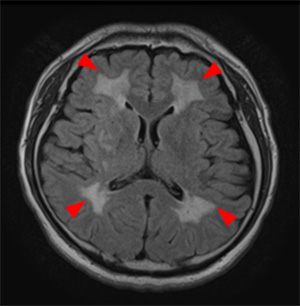

大脳白質病変

加齢や生活習慣に関連する脳小血管病の代表的変化です。軽度であれば加齢変化であり病的意義は少ないと思われますが、中等度以上になると脳卒中や認知症発症の危険因子と考えられます。その程度を示すために正確にはⅠからⅣまでのグレード分類が用いられますが、当脳ドックでは簡易的に軽度から中等度・高度とお示ししています。